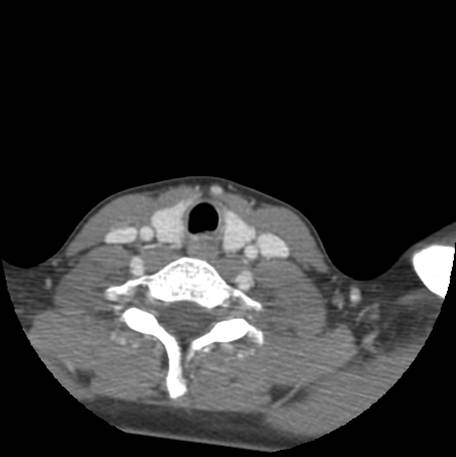

Fig.4a - normal epiglottis and arytenoids; Fig.4b - normal vocal cords, fullness seen below cords; Fig.4c - irregular mucosa in subglottic space with stenosis; Fig.4d-f - normal trachea below subglottic space with normal subsegmental bronchi (blood seen is iatrogenic related to procedure)

![]() Figure 5a |

![]() Figure 5b |

![]() Figure 5c |

Describe CT.